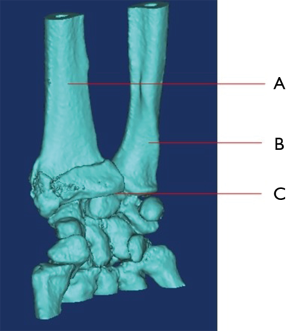

1.What’s name of bone that marked as “A”

- Ulna

- Radius

- Fibula

- Tibia

2. What’s name of bone that marked as “B”

- Ulna

- Radius

- Fibula

- Tibia

3. Which bone involves fracture?

- None of “A” and “B”

- Both of “A” and “B”

- Only “A”

- Only “B”

4. What’s name of the joint that marked as “C”?

- Knee Joint

- Elbow joint

- Ankle joint

- Wrist joint

5. What’s the name of bone that locates at proximal end of “A” and “B”?

- Femur

- Patella

- Humerus

- Scapula